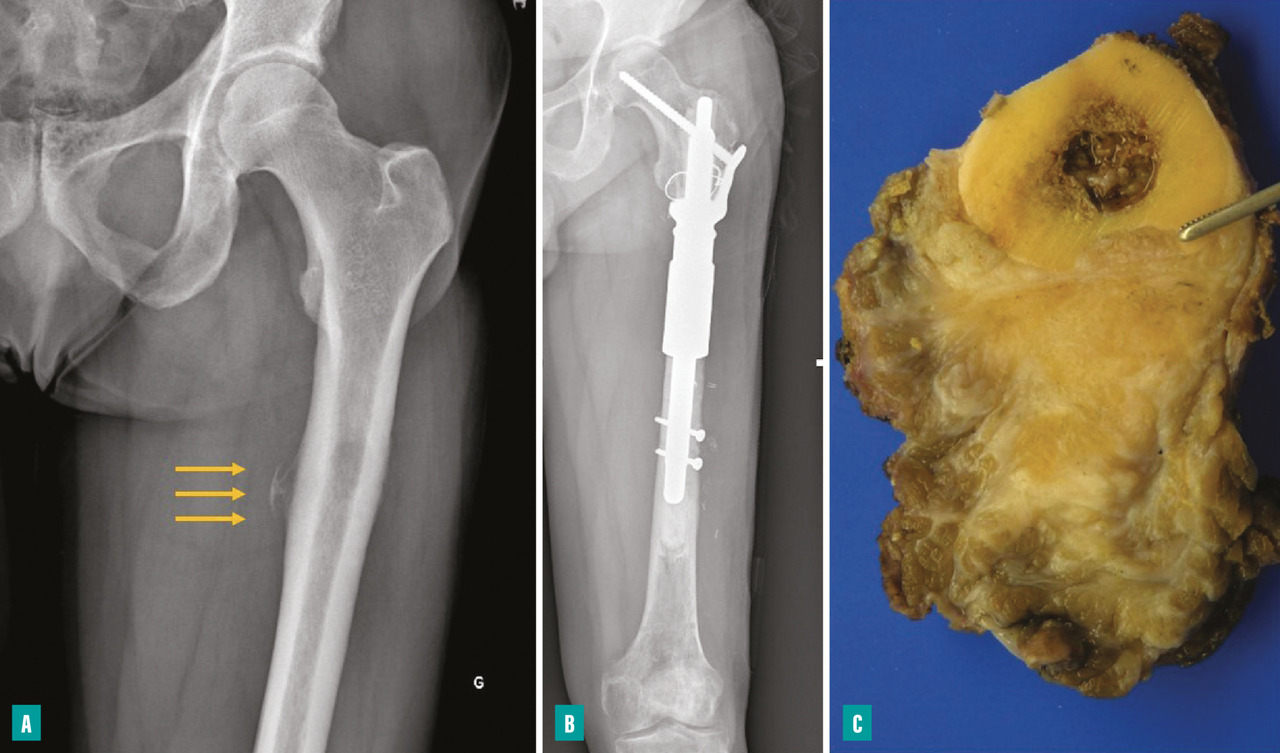

Pour les sarcomes des membres, la préservation de la fonction articulaire est le facteur déterminant. Dans la mesure du possible, les chirurgies avec préservation épiphysaire doivent être privilégiées (fig. 1). En cas d’atteinte épiphysaire, le choix de la technique opératoire dépend de la présence ou non d’un envahissement intra-articulaire, qui nécessite alors de recourir à une résection dite «  extra-articulaire  », techniquement plus exigeante (fig. 2). L’imagerie par résonance magnétique (IRM) a une place de choix pour identifier cette contamination articulaire.

La survenue d’une fracture pathologique rend plus difficile l’obtention de marges saines du fait de la dissémination de l’hématome dans les tissus mous. Elle ne semble pas augmenter le risque de récidive locale – à la condition d’obtenir des marges saines – et ne constitue donc pas une indication d’amputation (fig. 3). Lorsqu’elle survient en cours de traitement, elle fait craindre une mauvaise réponse à la chimiothérapie, qui pourrait expliquer le moins bon pronostic de ces patients.3,4